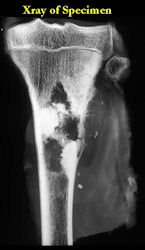

These are examples of the gross pathology specimens of resected conventional osteosarcoma, consisting of both bony and soft tissue areas. X-rays of the specimens are included.

- Osteosarcomas are composed of ossified or non-ossified tissue

- Ossified tissue is yellow-white and hard

- Less ossified tissue is soft and less yellow

- Non-ossified tissue is tan and fleshy

- Most (95%) of conventional osteosarcomas penetrate the cortex and form a large extraosseous soft tissue mass

- The lesion permeates the marrow spaces

- Osteosarcomas usually infiltrate the marrow several centimeters away from the main tumor mass

- Skip lesions may be apparent that are separated from the main tumor by normal marrow

- Osteosarcomas may also have cartilaginous components that appear as translucent lobules, and/or fibrous components that are tan, soft to firm rubbery areas

- Osteoblastic areas are usually white to yellow, firm, hard and gritty

- The consistency of the tumor depends on the amount of osteoid deposition, cartilaginous and fibrous areas

- Foci of hemorrhage and necrosis are common

- Periosteal reactions such as the Codman’s triangle are apparent at periphery of soft tissue mass

- Osteosarcomas rarely penetrate the growth plate grossly

- Invasion of the joint is uncommon but can occur by cortical penetration, joint capsule extension, or extension along cruciate ligaments

Gross Pathology: Osteosarcoma of Proximal Humerus

- originates from metaphysis of the proximal humerus, extends into surrounding soft tissues

- large soft tissue component that is crossing the glenohumeral joint

- was removed via an extra-articular resection, including scapula (Tikhoff-Linberg resection)